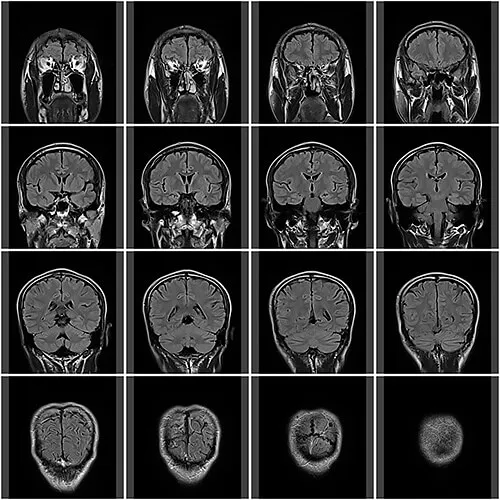

当院では、身体にやさしい、MRI装置(1.5T)を導入しています。

放射線を用いていないので、従来放射線をあてたくなかった部位の検査も安心して行うことができます。検査はベッドに横になっているだけで体の向きを変えることもなく、検査による苦痛はありません。

日本脳ドック学会が発行したガイドラインに準拠し皆様の健康維持のお手伝いをしたいと考えています。